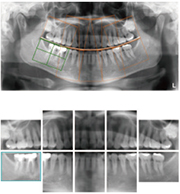

切片組合

全口影像顯示完成後,使用者可以自行設定裁剪區域,重新組合全口影像。可以依照根尖攝影的 10 張或 14 張的排列方式化分區域,然後在各個區域挑選最滿意的切片。